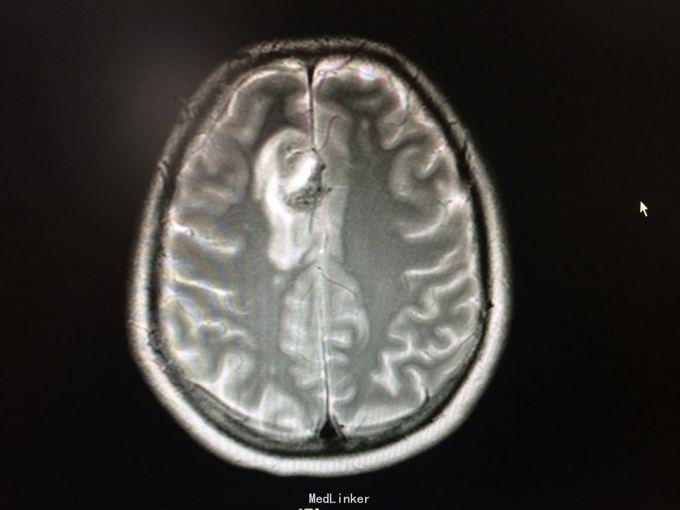

主诉:记忆力减退3月,左侧肢体乏力3天 病史:患者51岁女性,3月前无明显诱因出现记忆力减退,伴头痛,3天前出现站立不稳,左侧肢体乏力,步行困难,当地CT提示右侧额叶低密度灶,

查体:左侧上肢肌力4级,右侧5级,轻瘫试验左侧阳性 辅助检查:右侧额叶、胼胝体膝部病变伴出血,增强扫描明显强化。考虑胶质瘤

诊断:右侧额叶多发脑软化灶 处理:全麻下行右侧额叶占位病变切除术,术后病理提示:符合脑软化,未见明显肿瘤因素等